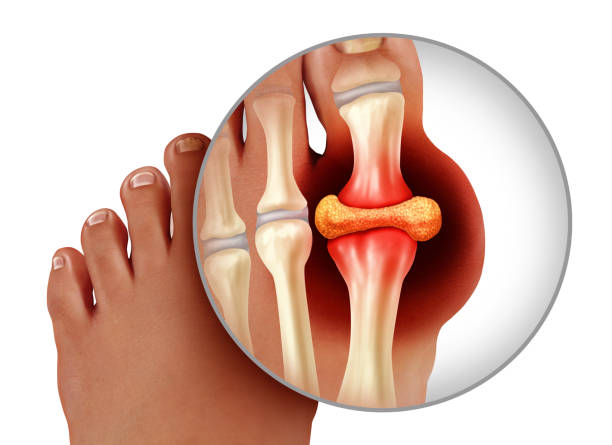

관절염 또는 통풍 등 염증성 질환

관절염이나 통풍과 같은 염증성 질환은 종자골염의 발생에 직접적인 영향을 줄 수 있습니다. 관절염은 발의 관절 주변에 염증을 유발하여 통증과 뻣뻣함을 유도하며, 이로 인해 보행 시 자세나 체중 분포가 비정상적으로 변하게 됩니다. 이러한 변화는 종자골 부위에 과도한 하중을 가하거나 마찰을 일으켜 염증이 발생하는 원인이 됩니다. 특히 류마티스 관절염은 발의 작은 관절까지 침범할 수 있어 종자골 주변 조직에까지 영향을 미치고, 통풍은 요산 결정이 관절에 쌓이면서 극심한 통증을 유발하는데 이 역시 종자골 부위에 통증과 염증을 촉진시킬 수 있습니다. 이러한 질환은 만성적으로 진행되기 때문에 발에 지속적인 염증 반응을 일으키고, 이에 따른 조직 손상이 반복되면 종자골염으로 이어질 가능성이 높습니다. 따라서 이러한 염증성 질환을 앓고 있다면 꾸준한 약물 치료와 함께 발에 무리를 줄이는 생활습관 관리, 기능성 신발 착용 등이 병행되어야 합니다.